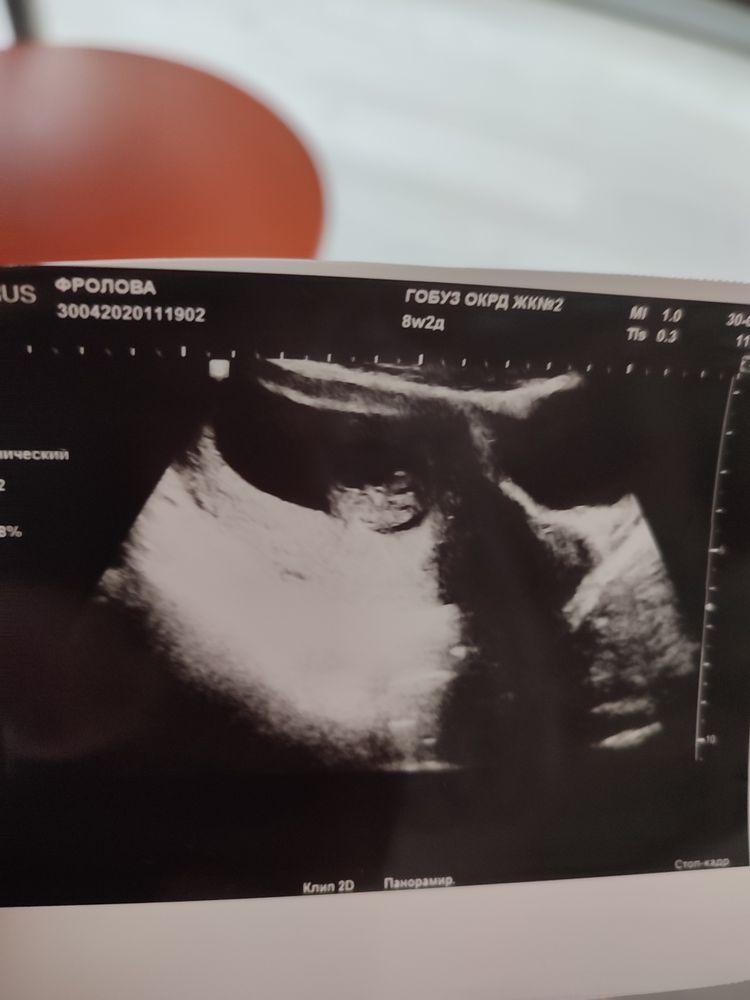

Вот доченька, 8.3 недель